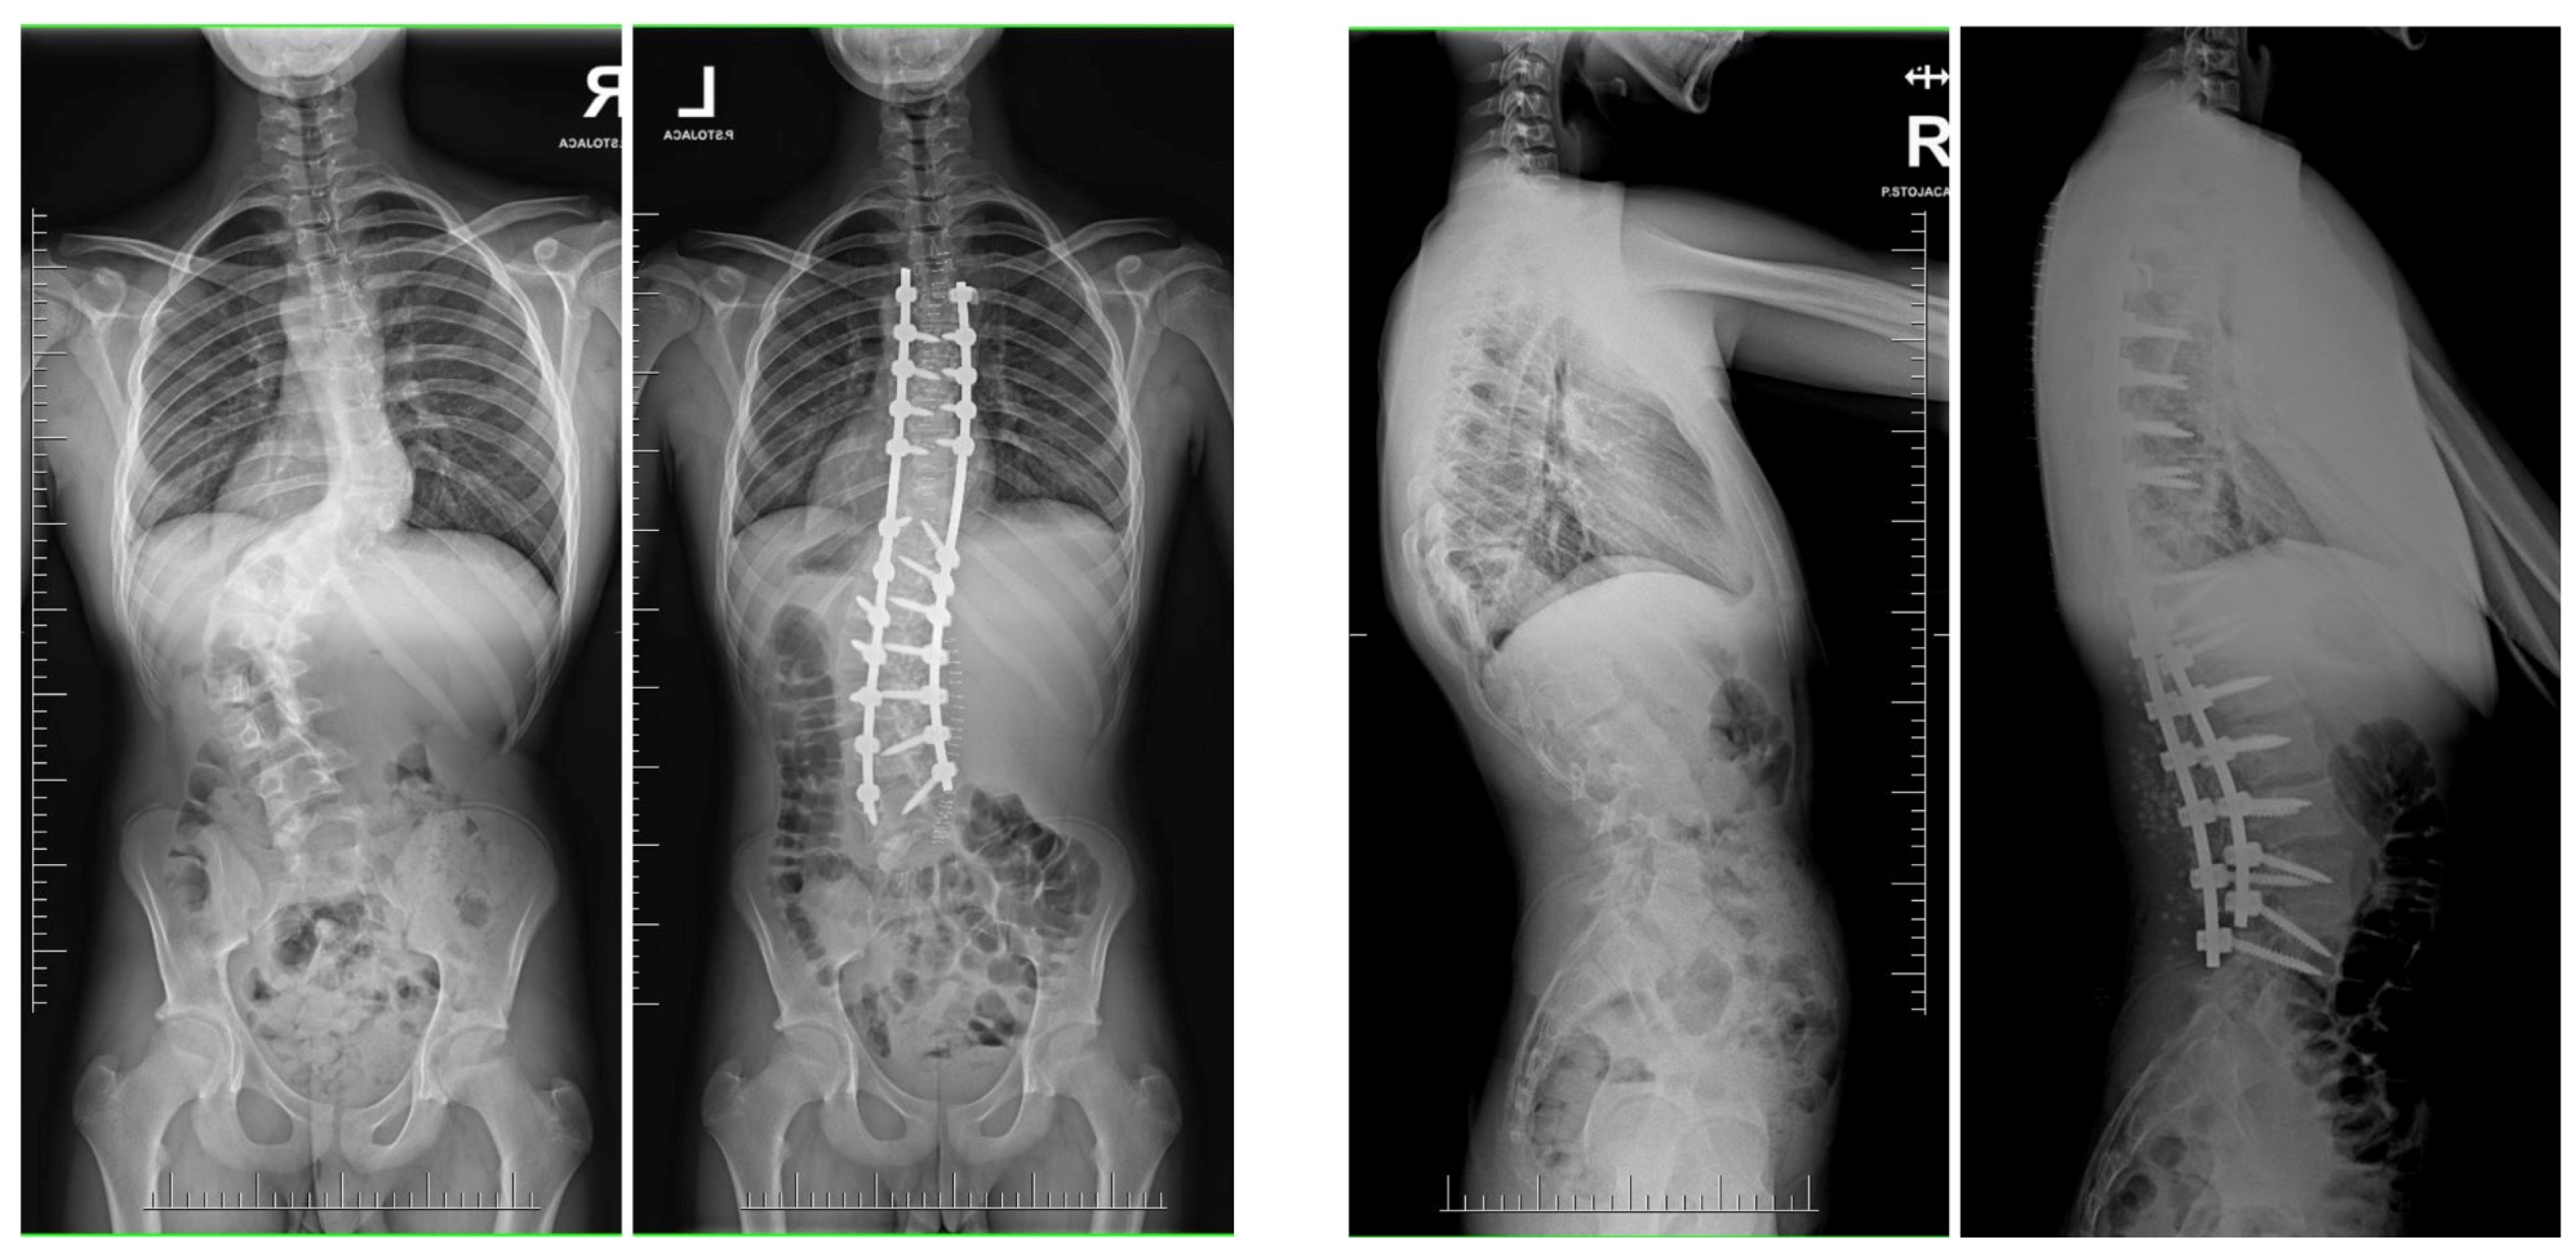

In the alternative approach delineated by Grabala et al. [44], patients were subjected to a two-phase surgical strategy. Initially, a comprehensive standard approach to the spine was carried out from the rear direction, enabling visualization of the spine at the specified stabilization levels. Facetectomy was performed at all spinal levels bilaterally, excluding the upper instrumented vertebrae (UIV). At all levels [73,74,75,76], a typical Ponte osteotomy was executed, with segmental screws being implanted at each level (at least on one side). A properly curved MCGR was positioned on the concave side of the curvature to achieve partial correction, while neuromonitoring guided the procedure. Pedicle screws on the convex side’s upper and lower levels were linked by a temporary short stabilizing rod, forming two firm blocks to strengthen the structure for future spinal distraction [44]. The patient was discharged after a five-day hospital stay, and weekly spinal distractions were performed over the next six weeks until reaching the maximum MCGR distraction point. Each distraction was carried out with maximum torque or until the observation of the “clunking phenomenon”. The forces applied during spinal distraction were of significant magnitude, and a single distraction control image was taken after six weeks of gradual lengthening of the magnetic rod. Subsequent to the completion of additional MCGR distractions, a final correction of the spinal deformity was conducted, involving the removal of the MCGR. The ultimate correction encompassed a blend of rod distraction/compression, apical translation, and segmental derotation. In the ensuing treatment phase, the resultant distraction length of the rod was measured using a ruler [44]. Figure 11 shows the treatment of a 16-year-old female diagnosed with severe adolescent idiopathic scoliosis with staged surgery, involving a temporary internal distraction device with MCGR for initial intervention, followed by PSF.

Figure 11.

During the observation period, pre- and post-operative radiographs were utilized to monitor the treatment progress of a 16-year-old female diagnosed with severe adolescent idiopathic scoliosis. Staged surgery was conducted, involving a temporary internal distraction device with MCGR for initial intervention, followed by the implementation of double Co-chr 6.0 rods for final correction of the spinal curvature.